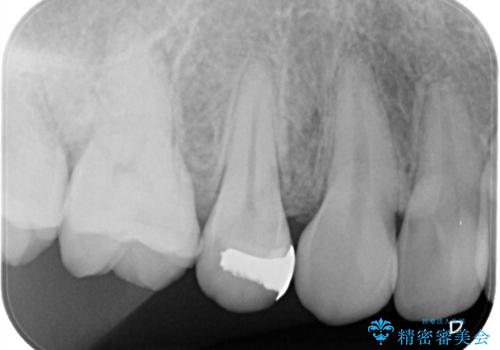

銀歯を除去し虫歯があるか確認し、虫歯がある場合は虫歯を取ってからセラミックが入るように形を作っていきます。

セラミックインレー(7万円)税別